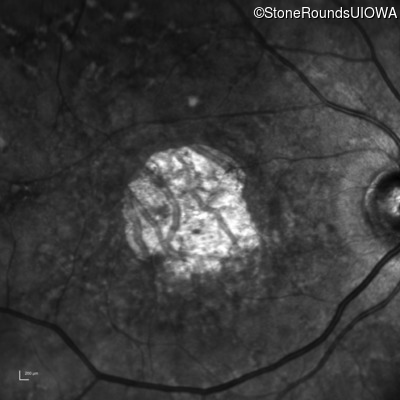

AR Stargardt Disease (IIA)

Age at visit: 54 years

Diagnosis & molecular findings

AR Stargardt Disease ABCA4 Glu471Lys GAA>AAA / Glu2131Lys GAA>AAA Asp2181 del36gaCCTGAACCCTGTGGAGCAGTTCTTCCAGGGGAACTT AR